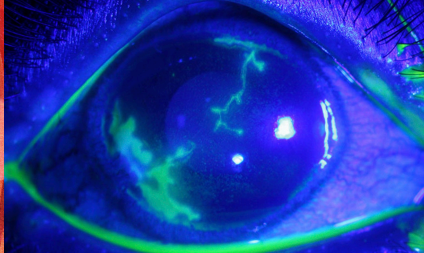

Diagnosis: fluorescein staining

➤ Dendritic corneal ulceration

➤ Slit lamp: increased fluorescein uptake

➤ Slit Lamp: dendritic uptake of fluoroscein

Diagnosis: clinical + fluoroscein staining

Clinical Manifestations ➤ Typically unilateral, **pain out of proportion to clinical findings**, decreased vision, ocular erythema, foreign body sensation, photophobia, tearing, mucopurulent discharge ➤ Slit Lamp: **radial or ring-like infiltrate**, **perineural infiltrates**